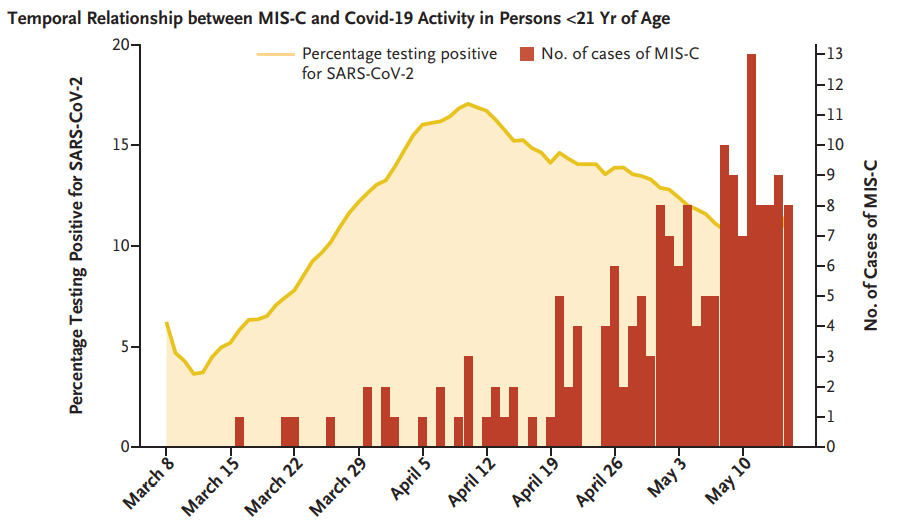

新冠引起的临床表现差异与年龄相关。成人出现呼吸症状,最严重的形式是急性呼吸窘迫综合征(ARDS),而儿童多出现胃肠道症状而非呼吸疾病,但可发展为危及生命的多系统炎...